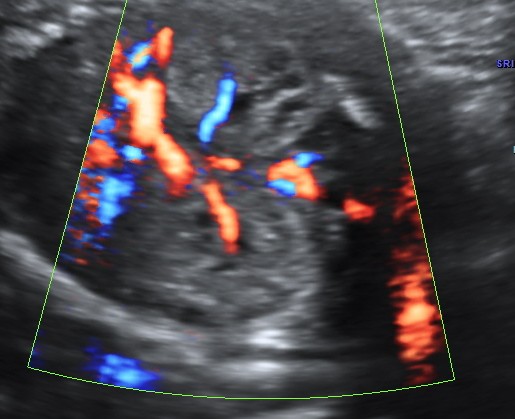

Placentomegaly with placental cysts

enlarged and hyperechoic kidneys